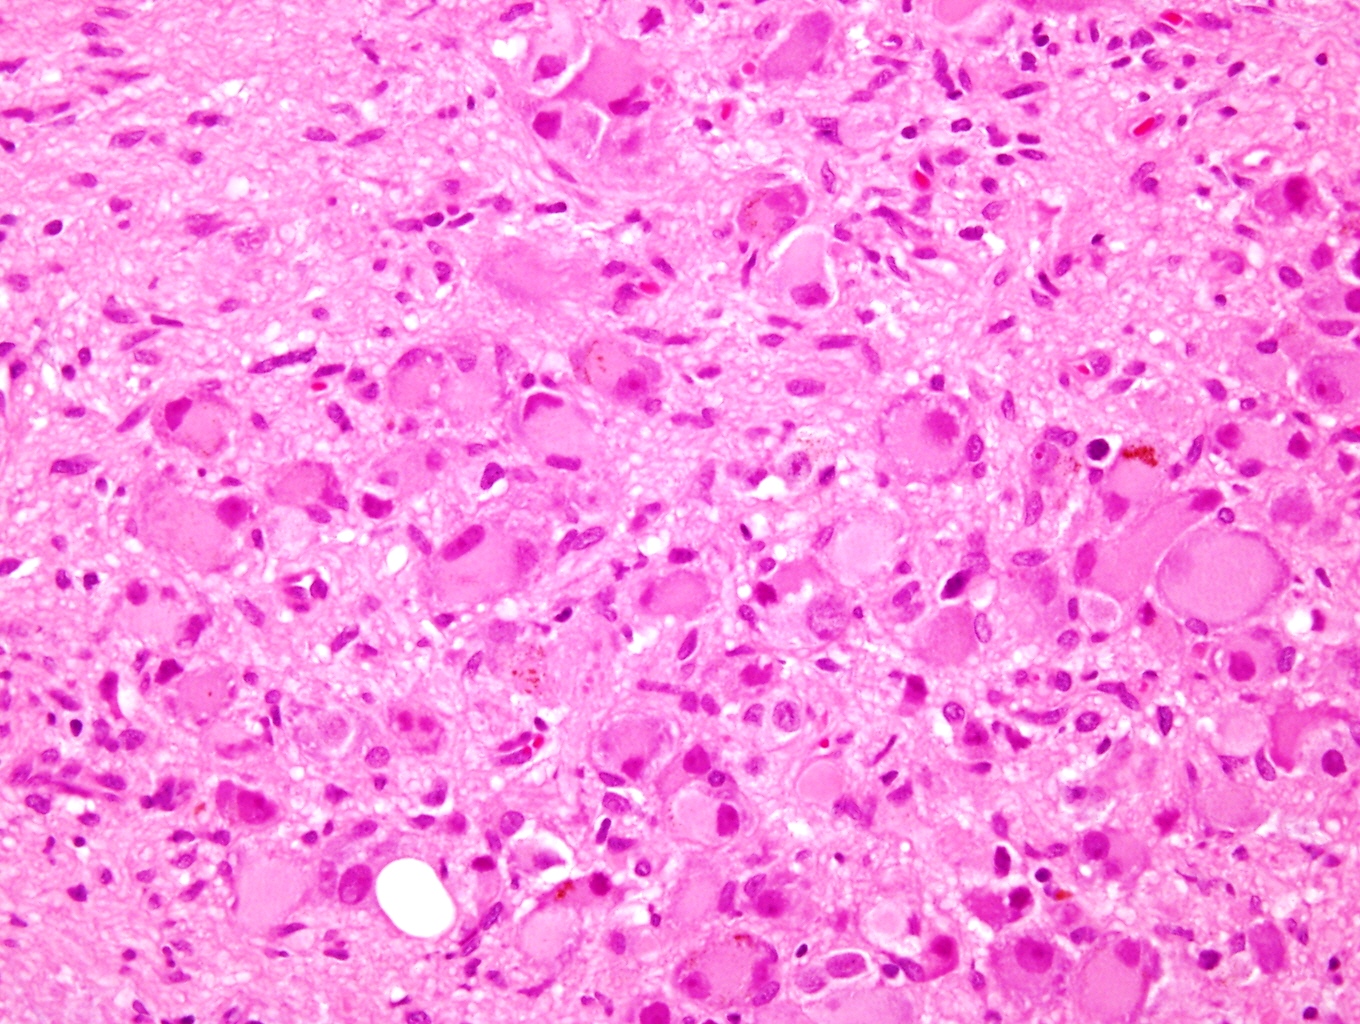

Microscopic (histologic) description

- Architecture: lobular, diffuse / solid, organoid

- Neuroblasts

- Homer Wright pseudorosettes = circular, ovoid, angular zones of pale staining neuritic cell processes surrounded by tumor cell nuclei; may rarely palisade

- Minimal cytoplasm, may have cytoplasmic tail

- Round to ovoid nuclei with stippled salt and pepper chromatin, inconspicuous nucleoli

- Ganglion cells

- Abundant granular eosinophilic cytoplasm (Nissl substance = rough endoplasmic reticulum)

- Distinct cell borders

- Nuclear enlargement, eccentric nuclei, prominent nucleoli

- May see neuromelanin pigment (brown, finely granular; rarely present), cystic degeneration, hemorrhage, dystrophic calcification

Microscopic (histologic) images

Contributed by Carmen Perrino, M.D. and Debra L. Zynger, M.D.

Intermixed type